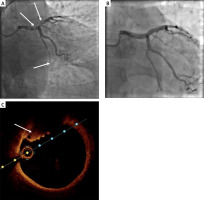

We present a case of a 45-year-old man, who was admitted due to anterior wall ST-segment elevation myocardial infarction of 3 h duration. Coronary angiography showed a normal RCA, thrombotic occlusion of the distal circumflex artery (Cx) and a massive thrombus in the distal left main artery (LM) protruding to the proximal left anterior descending artery (LAD) with preserved distal flow (Figure 1 A). Cautious, but unsuccessful thrombus aspiration (Hunter 6F) was performed. As the patient was stable he was qualified for further conservative treatment with administration of 72-hour infusion of eptifibatide, enoxaparin, acetylsalicylic acid and prasugrel. Echocardiography revealed extensive regional contractility abnormalities of the left ventricle with reduced ejection fraction (38%). Laboratory results showed a maximal troponin I (TnI) level of 83 355 pg/ml.

A – coronary angiography showing a massive thrombus in the distal left main coronary artery trunk, proximal left anterior descending and chronic total occlusion of distal left circumflex; B – coronary angiography eleven days after admission, no thrombus visible; C – optical coherence tomography showing a wall-mounted thrombus in the left main coronary artery trunk

After 4 days repeated coronary angiography showed only slight reduction of the thrombus. Based on this result the patient was discussed by the local Heart Team and qualified for pharmacotherapy continuation and another coronary angiography again in a few days.

Eleven days after admission, the second follow-up was performed, in which no LM thrombus was visible (Figure 1 B). OCT showed presence of a non-flow limiting fibrotic plaque (< 30% stenosis) in the LM and LAD with wall-mounted red thrombus and small elements of white thrombus (Figure 1 C). We did not observe plaque rupture, dissections or any other features of plaque instability. Taking the result into consideration the patient was qualified for conservative treatment without stent implantation.